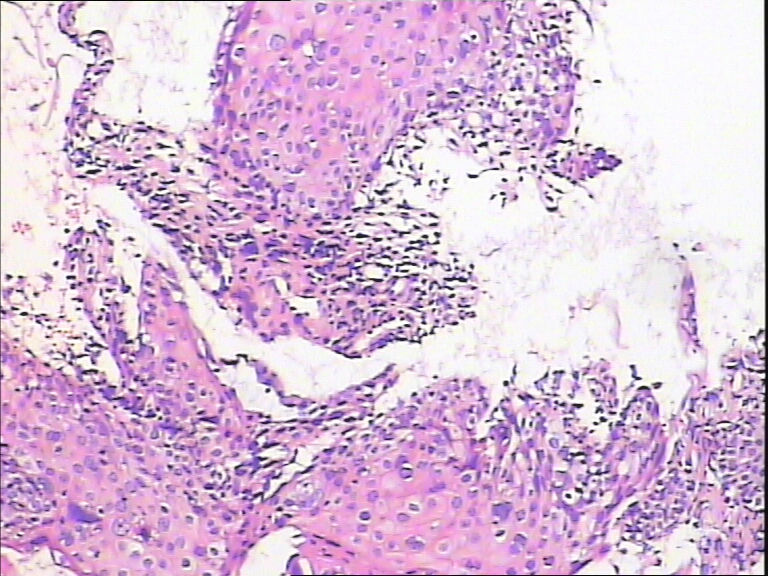

45y,触血,宫颈多点活检。

• 求教!宫颈图1

图1